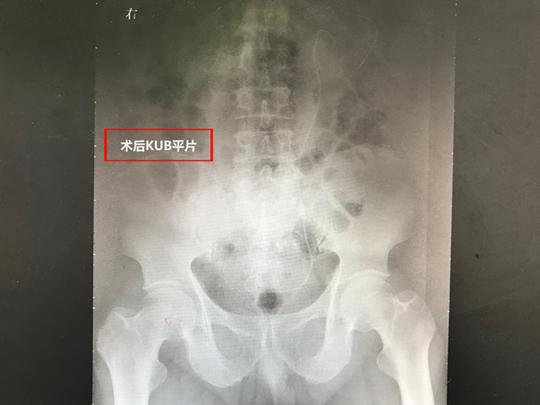

郁全胜团队医师经过严谨的术前讨论和精心准备,于11月28日为患者进行了微创经皮肾镜碎石取石术。术中郁全胜主任在熟练的B超引导下精准穿刺定位,成功建立穿刺通道,术中几乎无出血,为患者取尽了结石。患者目前正在康复中。

术后患者腰腹痛完善缓解,术后腹部平片结石取尽。